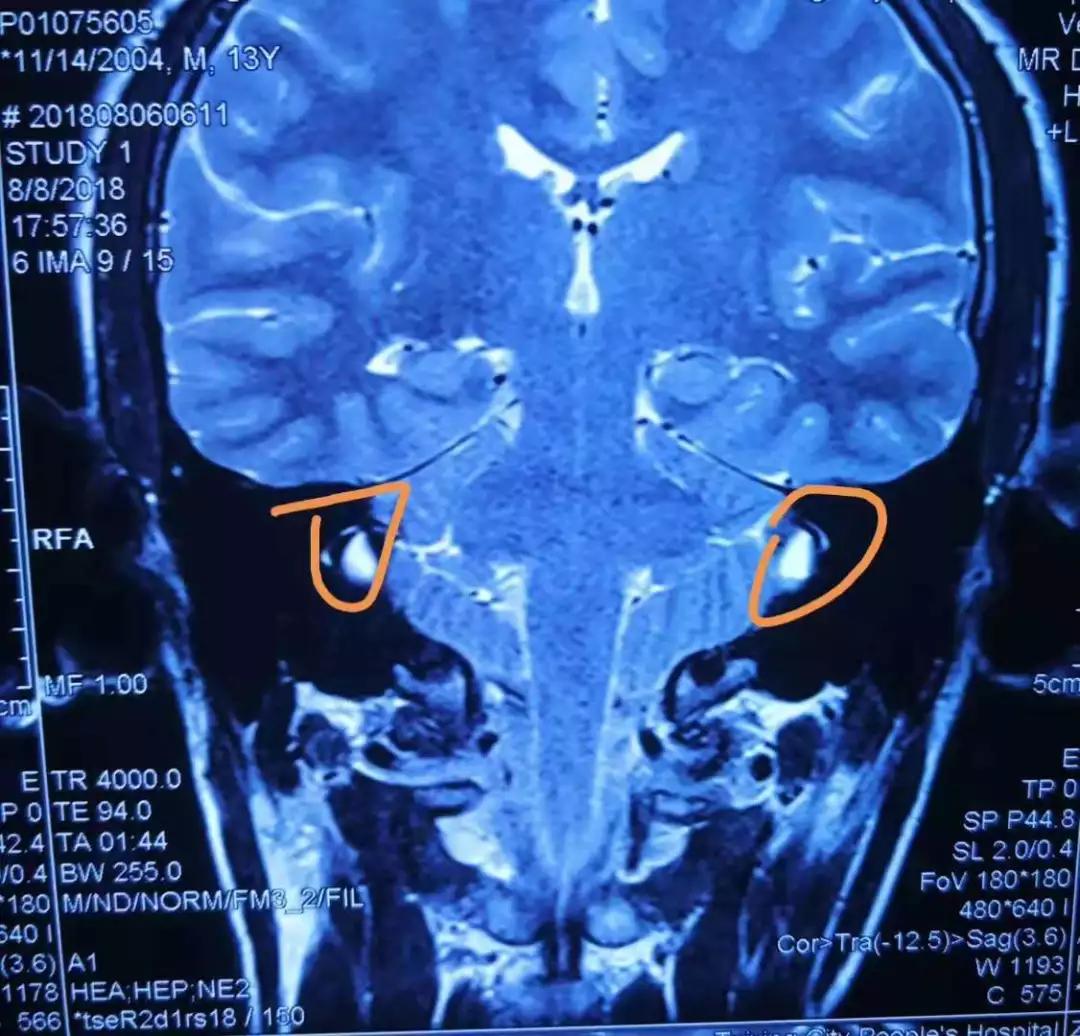

颞骨高分辨率ct示双侧前庭导水管扩大并与前庭池相通(图1a).